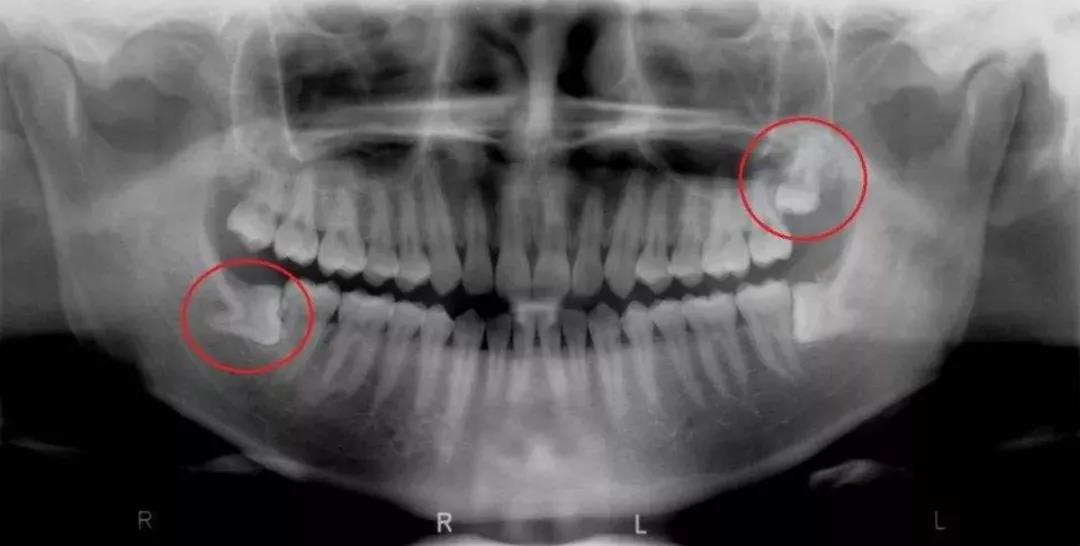

第二种是去医院拍CBCT牙齿全景影像片,通过专业的设备,可以很好的显示整口牙齿的分布状态,直观地看到自己有没有智齿,以及智齿的生长情况。

在这里建议大家采用第二种方法,去正规口腔医院拍牙片。

因为即便你的智齿没有萌出,肉眼无法看到,但在设备和片子里却可以明显地看出智齿在牙槽骨中位置,判断它是否会对口腔健康产生威胁。